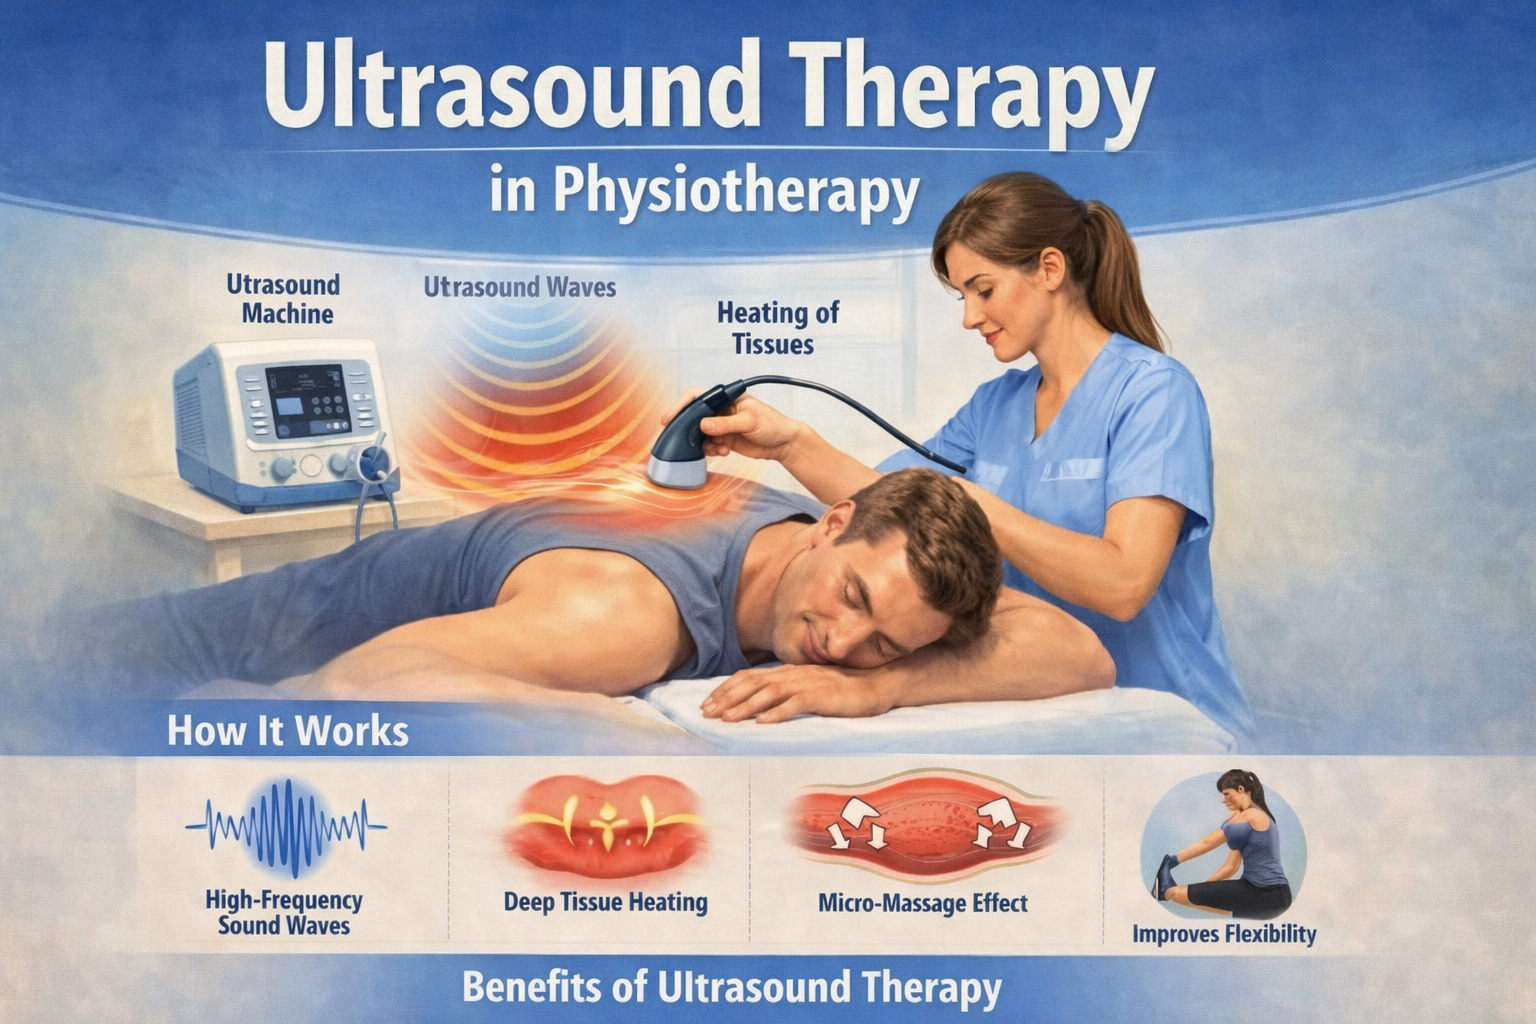

Prithivi Physiotherapy & Rehabilitation provides professional physiotherapy care for pain relief, injury recovery, and functional rehabilitation. Our goal is to help patients regain mobility, strength, and independence through evidence-based physiotherapy treatments and personalized rehabilitation programs.

✅ Evidence-Based Treatment

✅ Modern Physiotherapy Technique